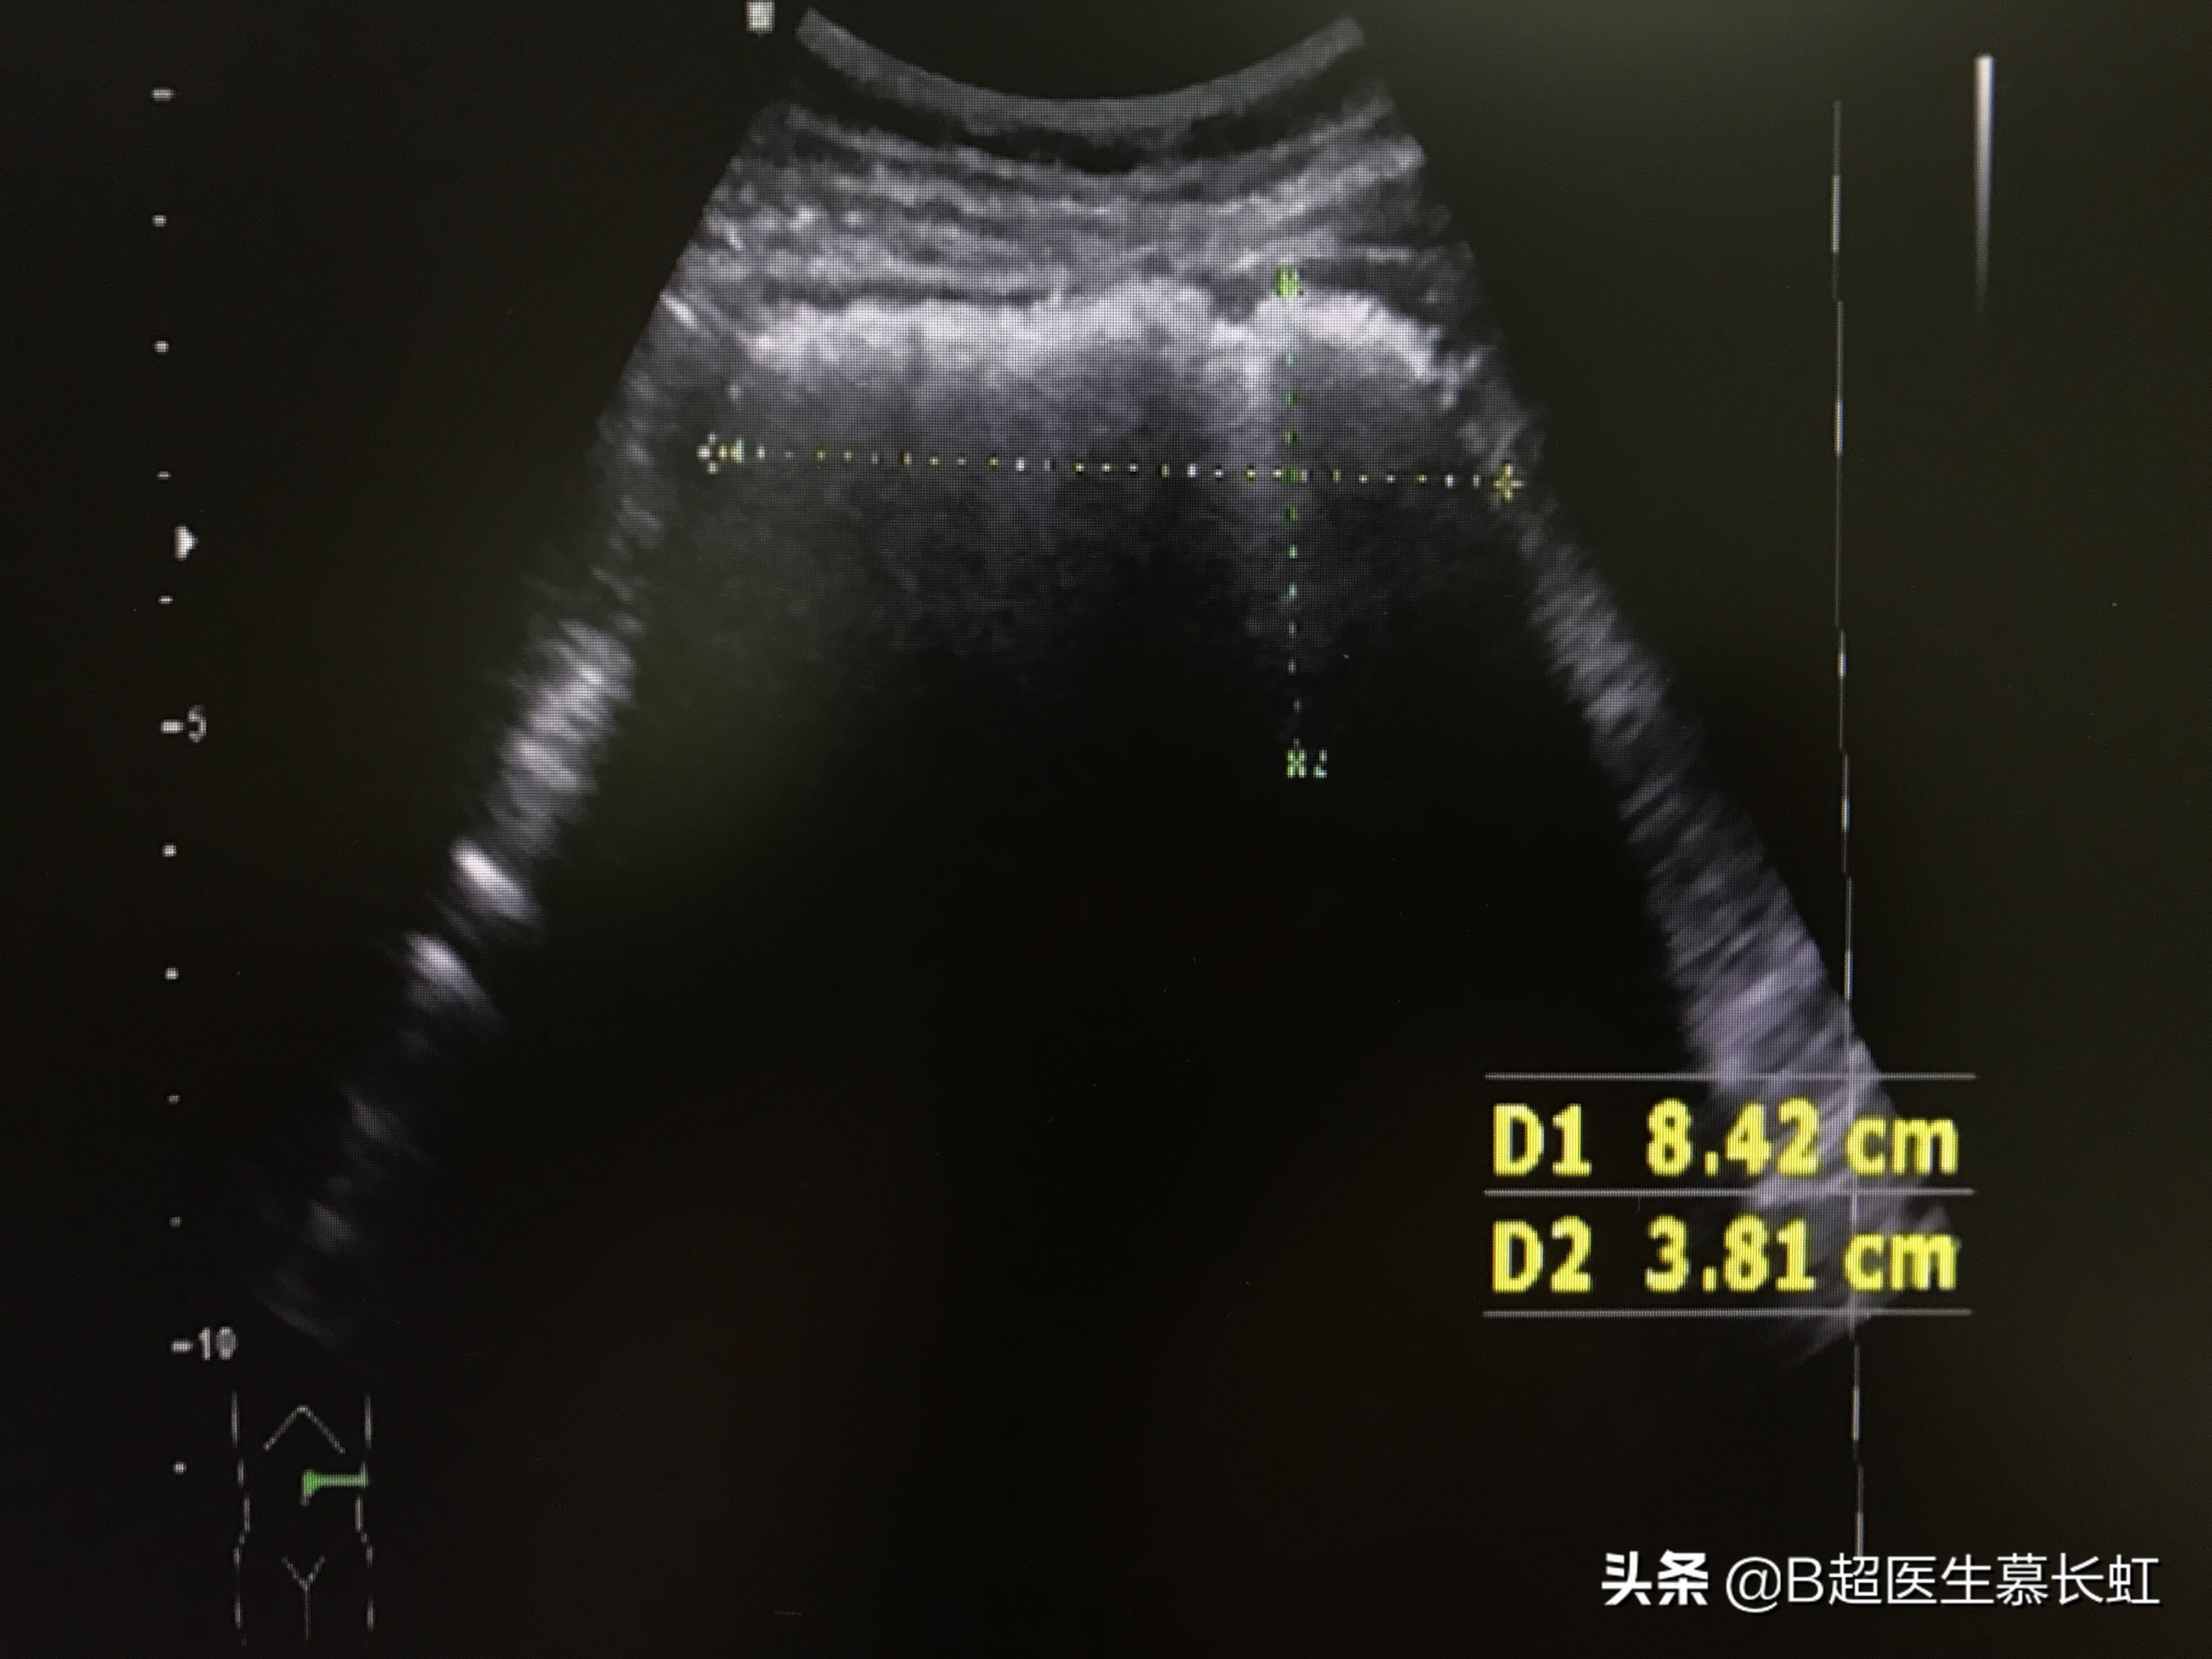

然后腹部全面扫查,发现肠管的确有异常。

从盲肠,升结肠,到横结肠,再到结肠脾曲。

就是围绕着腹部,从右下腹、右侧腹部、右上腹部、一直到左上腹部,肠管都是扩张着的,里面有杂乱的浑浊液体。